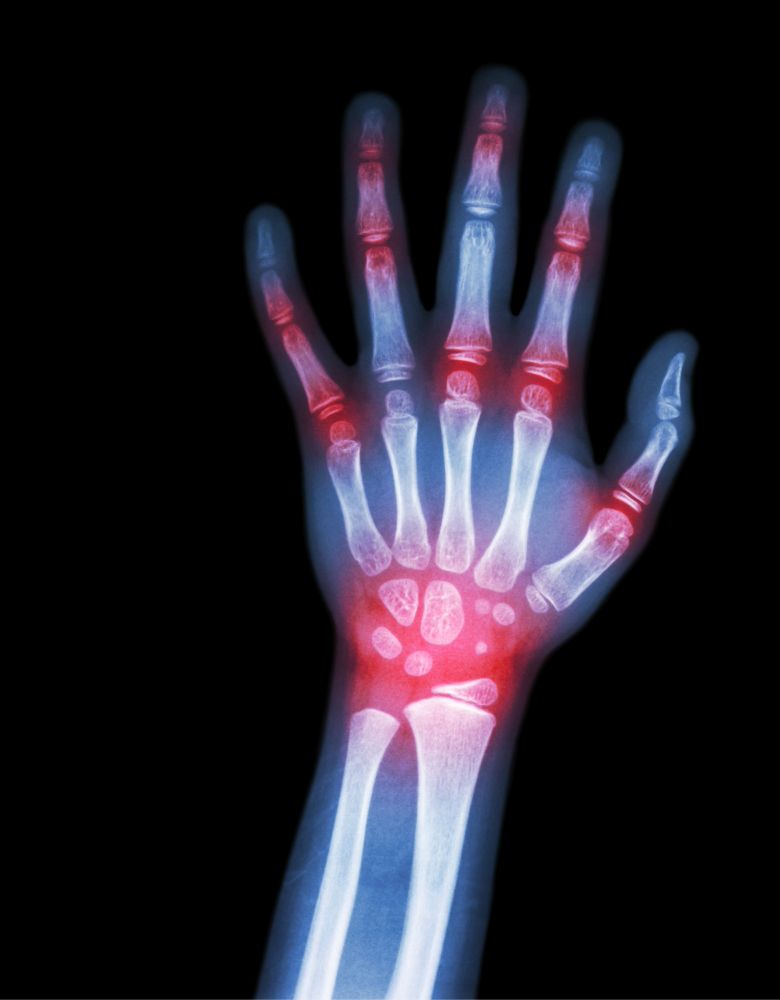

X-ray or CT/MRI

What imaging tests are needed before the surgery?

X-rays, CT scans, or MRI are used to understand the damage and plan the surgery with precision.